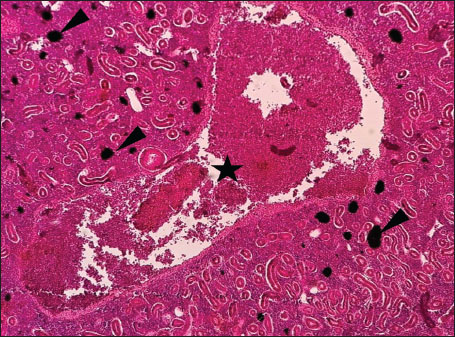

ABSTRACTBackground: The Mediterranean Sea has undergone significant ecological changes in recent decades, partly due to the introduction of non-native species. Lagocephalus sceleratus is an invasive Lessepsian species widely distributed in the Mediterranean, increasingly abundant along the Libyan coast, and potentially exposed to chronic environmental stressors. This species represents an important model for baseline pathological assessment in newly colonized marine environments. Aim: This study provides a descriptive histopathological assessment of kidney and gill tissues in adult L. sceleratus to document baseline tissue alterations without inferring direct environmental or pollution-related causation. Methods: A total of 150 adult specimens were collected from four Libyan coastal locations. Tissues were processed using standard histological techniques and evaluated semi-quantitatively (+, ++, +++) for lesion severity. Lesion severity grades were converted into ordinal numerical data and summarized using descriptive statistical approaches only. Results: Kidney tissues exhibited tubular degeneration, Bowman’s capsule dilatation, vascular congestion, extensive melanomacrophage centers (MMCs), and inflammatory lesions. Gill tissues showed disorganization of secondary lamellae, epithelial hyperplasia, edema, aneurysmal dilatations, vascular congestion, and MMC proliferation, some of which were associated with histologically observed parasitic structures. Conclusion: The observed alterations represent descriptive baseline tissue changes and should not be interpreted as direct evidence of pollution or specific environmental stressors. These findings provide reference data for future comparative pathological and ecological studies. Keywords: Lagocephalus sceleratus, Kidney, Gills, Histopathology, Melanomacrophage centers, Invasive species, Mediterranean Sea. IntroductionIn recent decades, the Mediterranean Sea has undergone profound ecological changes driven by the arrival and establishment of non-native marine species. Among these, Lagocephalus sceleratus has emerged as one of the most impactful Lessepsian migrants, due to its rapid geographic expansion, high ecological adaptability, and the presence of the potent neurotoxin tetrodotoxin in its tissues. This species has been widely documented to alter local fish communities, affect fisheries, and pose public health risks, making it an important target for biological and environmental assessment across the region (Katikou et al., 2022; Christidis et al., 2024). Fish are widely recognized as sensitive biological organisms in aquatic ecosystems, particularly in coastal habitats that are exposed to anthropogenic pressures such as industrial effluents, agricultural runoff, and untreated wastewater (Pinna et al., 2023). Among fish organs, the gills and kidneys are commonly regarded as sensitive to environmental stress, as they respond to physiological and pathological changes under environmentally suboptimal conditions. The gills, due to their large surface area and continuous exposure to surrounding water, are often the first tissues to exhibit structural alterations when fish encounter pollutants (Shahid et al., 2022). Histopathological changes in gills observed in polluted environments include epithelial lifting, lamellar fusion, hyperplasia, increased mucous cell density, and focal necrosis, which collectively reflect early physiological stress and potential compromise of respiratory function (Osman, 2010; Shahid et al., 2022). Similarly, the kidneys play crucial roles in osmoregulation, excretion of metabolic waste, and detoxification, making them highly vulnerable to chronic or systemic toxic effects (Wahidi et al., 2025). Documented renal lesions associated with chemical exposure include tubular deterioration, glomerular shrinkage, interstitial edema, and infiltration of inflammatory cells. These structural alterations often coincide with underlying biochemical disruptions, such as oxidative stress, impaired detoxification pathways, and activation of apoptotic mechanisms (Bernet et al., 1999; Authman, 2015). Despite the growing body of research on the ecological and toxicological implications of L. sceleratus, detailed histopathological assessments of this species remain scarce, especially in the southern Mediterranean basin, where environmental conditions and pollution profiles may differ from those in other regions. To date, detailed tissue-level studies of L. sceleratus from the southern Mediterranean are lacking, which limits the understanding of how this invasive species responds physiologically to local environmental stressors (Shakman et al., 2019; Ulman et al., 2021; Mohmmed et al., 2023). Accordingly, the present study aims to provide a comprehensive descriptive evaluation of histopathological changes in the kidneys and gills of L. sceleratus. The study is designed as a baseline histopathological assessment, focusing on tissue-level alterations without establishing causal links to environmental pollution or physicochemical stressors. By documenting structural aberrations and pathological features, this study contributes reference data for future monitoring and comparative studies in Mediterranean coastal ecosystems. Materials and MethodsSample designA total of 150 adult specimens of L. sceleratus, including both sexes, were collected from four Libyan coastal locations: Talamitha (n=39), Susah (n=34), Ain El-Ghazala (n=30), and Khalij Al-Bambah (n=47). Fish ranged in total length from 51 to 66 cm and in weight from 1.5 to 3.5 kg. Only apparently healthy adults were included, while juveniles were excluded to avoid age-related histopathological variation. Sampling was conducted opportunistically with assistance from local fishermen. All specimens were collected within a comparable seasonal window to minimize seasonal histopathological variability. Sex was recorded when possible; however, sex-based histopathological comparisons were not performed, as this was beyond the descriptive scope of the study. Fish were transported on ice at +4°C and examined in the Pathology Laboratory, Faculty of Veterinary Medicine, Omar Al-Mukhtar University (Mohmmed et al., 2023). Specimens were collected from a range of depths (0.5–70 m), with the majority from shallow waters (<10 m) and a subset (approximately 50 fish) from deeper locations (>30 m). Environmental physicochemical parameters such as temperature, salinity, and dissolved oxygen were not measured; therefore, no direct associations between histopathological findings and environmental variables were assessed. Tissue processing and histopathological examinationTissue specimens were fixed in 10% neutral buffered formalin for 24 hours. Following fixation, the samples were transferred to 70% ethanol for storage at room temperature. Subsequently, the tissues were processed for routine histopathological examination following standard procedures (Paul and Chanda, 2017). Paraffin embedding was performed, and 5 µm-thick sections were prepared using a microtome. Sections were stained with hematoxylin and eosin (H&E) and examined under a light microscope. Photomicrographs of representative lesions were captured using a high-resolution digital camera. Histopathological alterations were evaluated using a semi-quantitative scoring system adapted from Hose et al. (1996), Moshaie-Nezhad et al. (2021), and Alshailabi et al. (2023), where lesion severity was graded as mild (+), moderate (++), or severe (+++). Lesion severity grades (+, ++, +++) were converted into ordinal numerical values (1–3) for descriptive summarization of lesion severity. Due to the descriptive baseline nature of the study and the absence of a reference control group, inferential statistical comparisons were not emphasized or applied. Lesion severity scores were therefore summarized descriptively to avoid overinterpretation of the findings. Scoring was performed independently by two experienced observers, and representative lesions were confirmed across three sections per organ to ensure consistency. Tissues with visible parasitic structures were described separately from non-parasitized tissues to avoid conflating parasite-associated lesions with non-specific tissue alterations. The functional implications of the observed lesions were interpreted in accordance with Flores-Lopes and Thomaz (2011). Ethical approvalAll animal experiments conducted in this study were approved by the Ministry of Higher Education & Scientific Research and the Libyan National Committee for Biosafety & Bioethics, Libya. All procedures were performed in accordance with the relevant ethical guidelines, with session number 21/CH/25, dated 26/05/2021. ResultsHistopathological examination of the kidneyHistopathological examination of the kidney tissues of L. sceleratus revealed multiple alterations. Prominent melanomacrophage centers (MMCs), necrotic areas, dilatation of Bowman’s capsules, and vacuolar degeneration were observed (Fig. 1), associated with interstitial lymphohematopoietic tissue (Fig. 2). Dilated and congested blood vessels and extensive MMCs were also noted (Fig. 3). Renal degeneration surrounding lymphohematopoietic tissue, large clusters of MMCs, and thickened, congested vessel walls within fibrotic areas were evident (Fig. 4). Atrophic renal degeneration with necrotic and vacuolar changes was observed (Fig. 5). Severe inflammatory infiltration of lymphatic cells and granulomas with necrotic centers, surrounded by fibrous tissue, was detected (Figs. 6–7).

Fig. 3. Histopathology of the kidney in an adult L. sceleratus showing dilated and congested blood vessels (star) and severe MMC proliferation (head arrows). ×40 H&E.